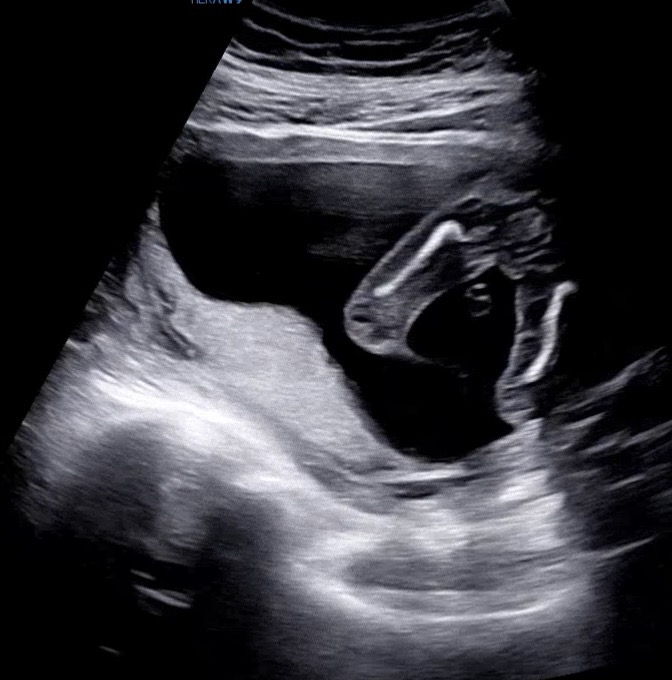

아들일까요? 딸일까요?!

오늘 초음파 보고왔는데, 선생님은 딸로 보인다구 하긴하셨는데!! 혹시 성별반전은 없겠죠?! 딸이 맞겠죠?!

아들이였으면 다리사이에 분명하게 보였을거에요 아무것도 없으니 딸같아요

우리딸도 이랬어요 ㅋㅋ 딸같은데요?